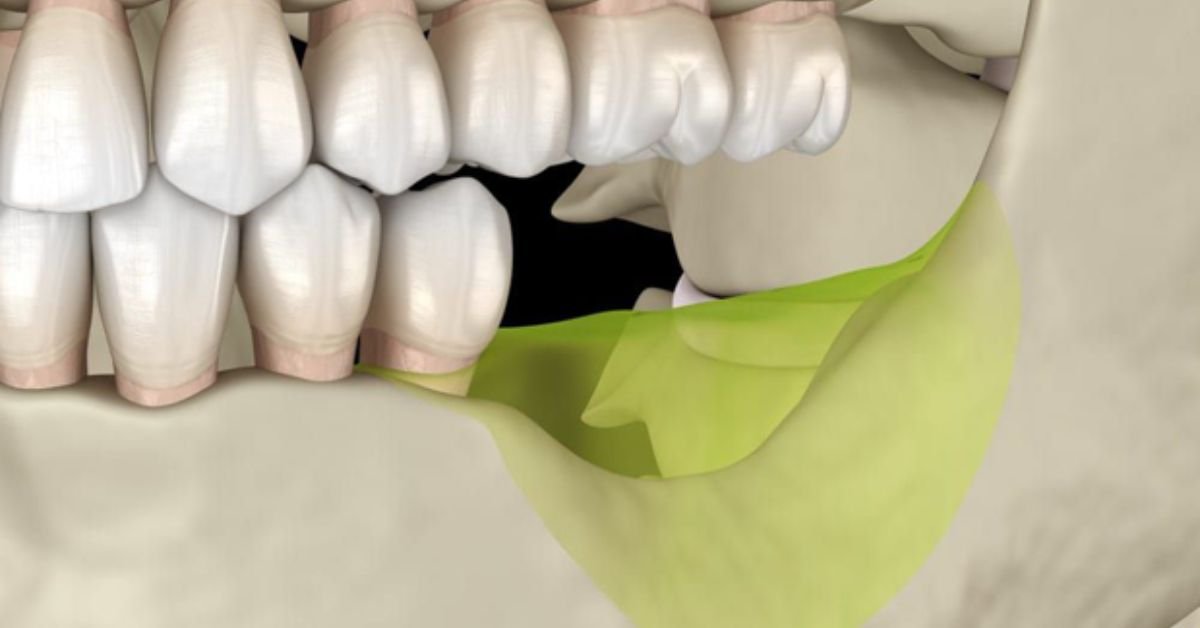

- Preservação dos Tecidos: A presença imediata de um dente provisório ajuda a guiar a cicatrização da gengiva, mantendo seu contorno natural e estético. Isso é chamado de “condicionamento gengival”.

- Alta Satisfação do Paciente: A percepção de um tratamento rápido, eficiente e com resultado estético imediato gera uma experiência extremamente positiva.